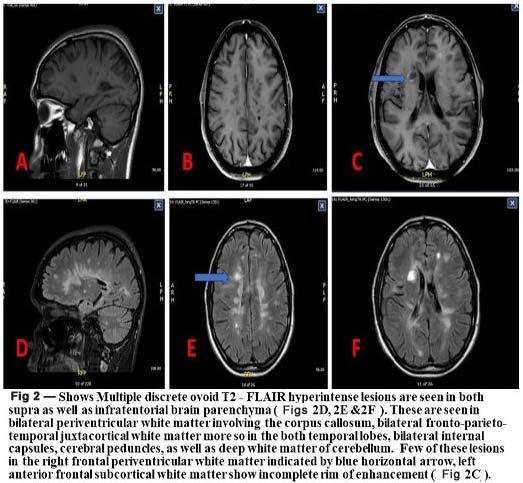

Alarming rise in mucormycosis cases in postCOVID-19 phase has stressed to think some triggering causative factors beyond the steroid use and immunocompromised status by diabetes mellitus or other diseases8. Diagnosis by MRI, superintendence of contributory factors, Functional Endoscopic Sinus Surgery (FESS)5, conservative management by antifungal drugs and surgical debridement are the best treatment protocol2. The aim is to analyse 51 cases of mucormycosis for correlating between causative factors to help clinicians workout through the evolving disease pattern, considering the poor prognosis of the disease and its short time spread.